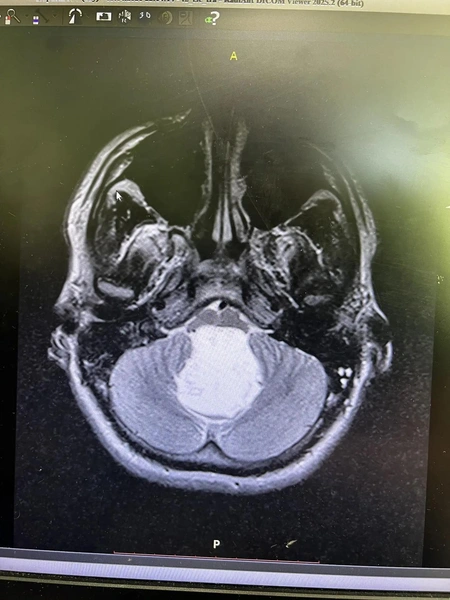

«Глядя на снимок, мы не поверили, что перед нами живой человек. Это было просто невероятно», — рассказал нейрохирург областной больницы Шалиндер Аул.

Оказалось, что у Никиты холестеатома, или эпидермоидная киста головного мозга. Это новообразование, которое еще называют «жемчужной опухолью» из-за характерного внешнего вида: она белая с перламутровым отливом. Это новообразование доброкачественное, но редкое и очень опасное.

«За двадцать лет это третий пациент с холестеатомой в моей практике. Когда мы вошли в зону вмешательства, то убедились своими глазами в том, что ствол мозга был передавлен опухолью. Останься он дома еще на сутки, и было бы поздно. Как потом показали результаты гистологии, у пациента врожденное доброкачественное новообразование, которому столько же лет, сколько молодому человеку», — Шалиндер Аул.